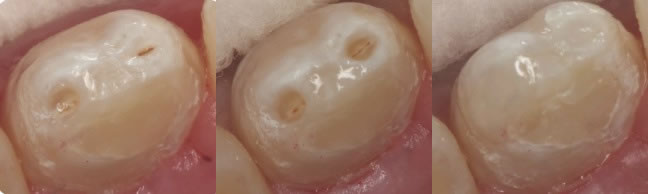

Figure 8: Incisal pits, Figure 9: Incisal pits prepped, Figure 10: Incisal pits bonded w/composite resin